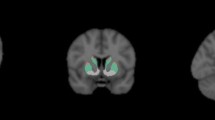

In a positive dopaminergic imaging PET scan, there is a decreased tracer uptake on one or both striata, with an oval or circular shape. An asymmetric pattern of reduced putamen and preserved caudate uptake showing a caudate to putamen posterior-anterior gradient or dot shape is most consistent with parkinsonism syndromes (Fig. 13.10). The locus coeruleus and substantial nigra nuclei may become more visible in nigrostriatal degeneration cases (Figs. 13.11 and 13.12).

FDOPA-PET/MRI demonstrates a positive dopaminergic imaging PET scan. The (a) axial images and (b) coronal images show asymmetric reduced tracer uptake in the putamen, more pronounced in the posterior part creating a posterior-anterior gradient (read arrows) with preserved bilateral tracer uptake in the caudate (white arrows) and right putamen (black arrows). (Courtesy of Dr. Juan M. Chomont, Chief of Radiology at INTECNUS, S.C. de Bariloche, Argentina)